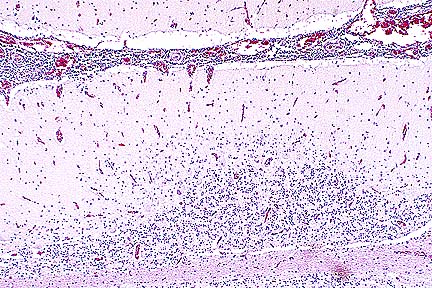

Numerous PAS-positive neuronal and glial inclusions in the cerebellum of a Maine Coon cat with tremors and seizure-like activity. (PAS, 100X, 65K)

Higher magnification of the field above, showing cytoplasmic inclusions within several Purkinje cells, as well as inclusions in unidentified cells in the molecular layer. (HE, 400X, 48K)

Contributor's Diagnosis and Comments: Cytoplasmic polyglucosan inclusions (Lafora bodies) within neuronal perikarya and processes, most numerous in Purkinje cells.

In sections of brain, there are few to many basophilic to amphophilic inclusions that occur within the cytoplasm of nerve cell bodies, neuronal processes, and scattered in the neuropil. These inclusions are usually round, range in size from 2 to 10 um diameter, and occasionally have a pale center or a thin, striated halo. These Lafora-like bodies are most numerous in the cerebellar molecular layers and within Purkinje cells, but are observed in all examined sections of brain.

Lafora bodies consist of complex polymers of glycoprotein, sometimes designated "polyglucosan bodies", and can occur within neuronal cell bodies or processes of the brain, spinal cord, or retinal ganglia. The round to globular basophilic cytoplasmic inclusions stain positively with PAS, alcian blue, and methenamine silver. In domestic animals, Lafora bodies have been observed most commonly in aging (at least 8 years of age) dogs and cats without apparent neurologic disease, but have also been described as incidental changes in some young animals. Lafora bodies have also been associated with a severe form of progressive myoclonus epilepsy in humans (juveniles) and dogs (young adult to middle-age), reflecting widespread intra-neuronal storage of these polyglucosans ("Lafora disease" or "neuronal glycoproteinosis"). The absence of other lesions to account for the observed neurologic signs incriminates the Lafora bodies as playing a role in the reported neurologic signs in this cat. In dogs with associated neurologic disease, the deposits are most commonly observed in Purkinje cells, similar to the distribution noted in this cat. In children with Lafora disease, other sites of polyglucosan deposition include skin and liver, and biopsies of these tissues have been used to help establish the diagnosis. Lafora bodies were not found in tissues from other than the CNS in this cat.

AFIP Diagnosis: Cerebellum, molecular and Purkinje cell layers: Polyglucosan bodies (Lafora bodies), neuronal and extracellular, diffuse, numerous, Maine-Coon, feline.

Conference Note: This case was also reviewed by AFIP's Department of Neuropathology. Lafora bodies are complex glycoprotein neuronal inclusions that can occur in the perikaryon, dendrites, or axons. They are PAS-positive and stain with alcian blue and methenamine silver. They can be found anywhere in the neuraxis and in retinal ganglion cells. Polyglucosan bodies have been associated with neurologic disease in humans, cats, dogs (Beagles, Basset Hounds, and Poodles), and a cockatiel. Lafora's disease in humans is a rare familial neurologic disorder of children. The disease is progressive and manifested by myoclonus. The characteristic histologic feature in the human disease is intraneuronal polyglucosan bodies, which occur predominantly in the substantia nigra and dentate nucleus. In dogs with neurologic disease attributed to the accumulation of intraneuronal polyglucosan bodies, the bodies are found predominantly within Purkinje cells and in thalamic neurons. In animals, Lafora bodies are frequently seen in the absence of neurologic disease. In these cases, the Lafora bodies can be found in any area of the brain and in the spinal cord.